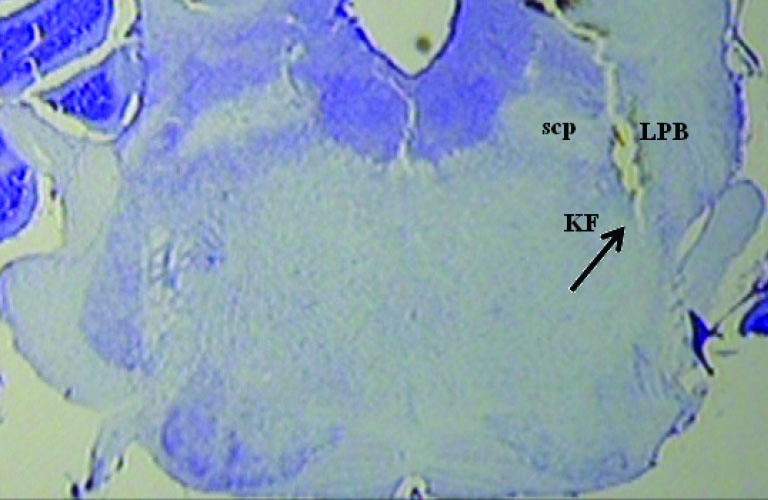

A photomicrograph with two injection sites is displayed in Fig. 7. The diagrammatic representation base on rat brain atlas is shown in Fig. 8. Data of the injection sites outside the KF were not included in the analysis.

Fig. 7.

A photomicrograph with injection site. scp: superior cerebellar peduncle, LPB: lateral parabrachial nucleus.